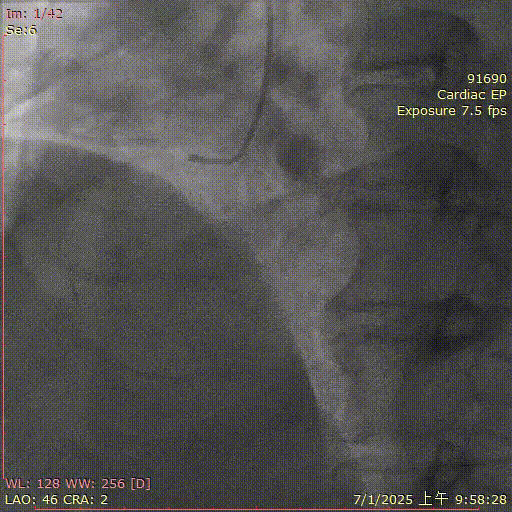

金叔宣教授团队

基本情况:患者,男,64岁,因“活动后胸闷心悸1年”入院。

简要病史:2018年6月心梗置入2枚支架,8月再次置入3枚支架(手术记录不祥),2024年再次出现活动后胸闷心悸,2025年1月造影提示前降支开口至中段原支架内再狭窄,最重狭窄95%,右冠脉中段闭塞,见回旋支提供侧枝供应远段,成功药物球囊处理前降支支架内再狭窄,择期处理右冠CTO。J-CTO评分4

辅助检查:LVEF 58%,Scr 105

术前诊断:陈旧性心肌梗死,冠状动脉支架植入术后状态,心功能NYHA Ⅱ级,高血压,2型糖尿病

术前造影